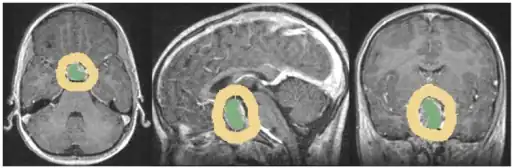

The differential diagnosis includes pituitary tuberculoma, especially in developing countries and in immumocompromised patients.[46] The diagnosis is confirmed by testing hormone levels, and by radiographic imaging of the pituitary (for example, by CT scan or MRI).